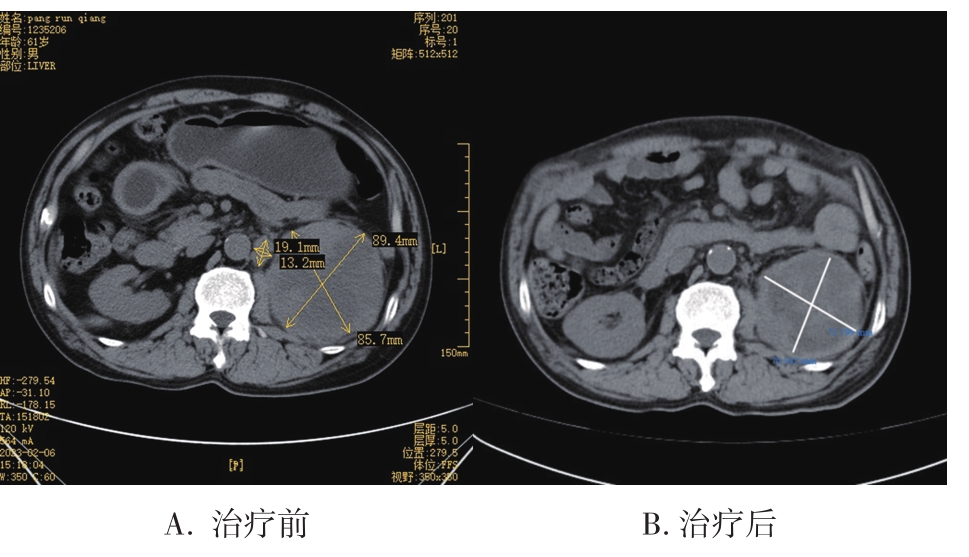

• 转移性上尿路上皮癌在维迪西妥单抗联合替雷利珠单抗新辅助治疗后行根治性肾盂癌切除术1例报道

2023, 48(8):1005-1008. DOI: 10.13406/j.cnki.cyxb.003299

摘要 (52) HTML (36) PDF 2.16 M (1929) 评论 (0) 收藏

摘要: